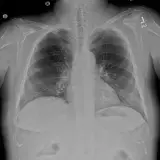

Casos totalmente interactivos con las herramientas que esperaría de un PACS: scroll, ventana, zoom, pan, mediciones, ROI y modo de pantalla completa.

• Anotaciones enlazadas

Anotaciones extensas resaltan los hallazgos clave directamente sobre los casos. Haga clic en los hallazgos enlazados dentro de la descripción del caso para saltar a su ubicación exacta en el estudio.